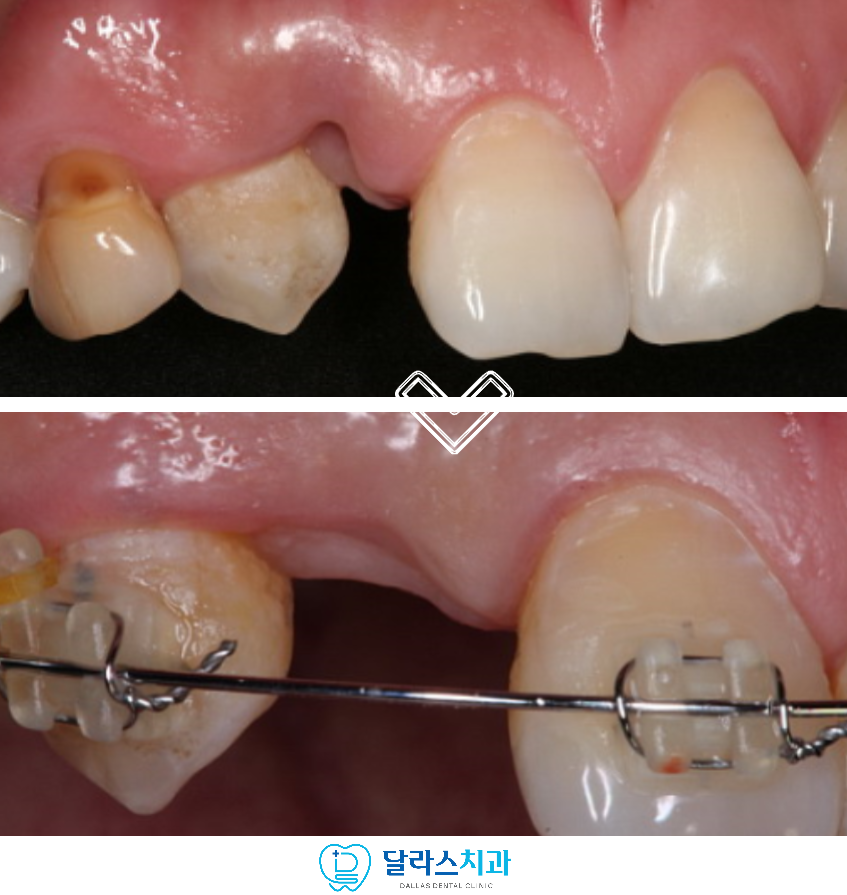

저희 노원치과 달라스치과에서 치료를 진행한 증례에서는

만기 잔존 유치로 인해 오른쪽 두 번째 앞니 부위의 식립 공간이 부족한 상태였습니다.

씹는 부분에서 바라보면

유치 자체도 크기가 작기 때문에 공간이 매우 부족합니다.

환자분과 충분한 상의를 통해서 안정적이고 심미적인 임플란트 결과를 위해

교정을 우선적으로 시행하여 인접 치아를 이동시켜

필요한 폭을 확보하는 것으로 계획하였습니다.

교정 장치를 부착하여서 기존보다 약 3배 이상 되는 공간을

확보한 이후에는 임플란트를 식립하였습니다.